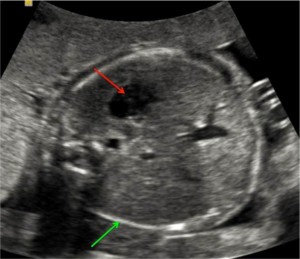

این تصویر نمونه ای از بررسی جنین در هفته 21 بارداری است. می توانید به راحتی پیشانی، بینی (فلش قرمز)، لب ها و چانه (فلش سبز)، پس گردن و بخشی از قفسه سینه را شناسایی کنید.